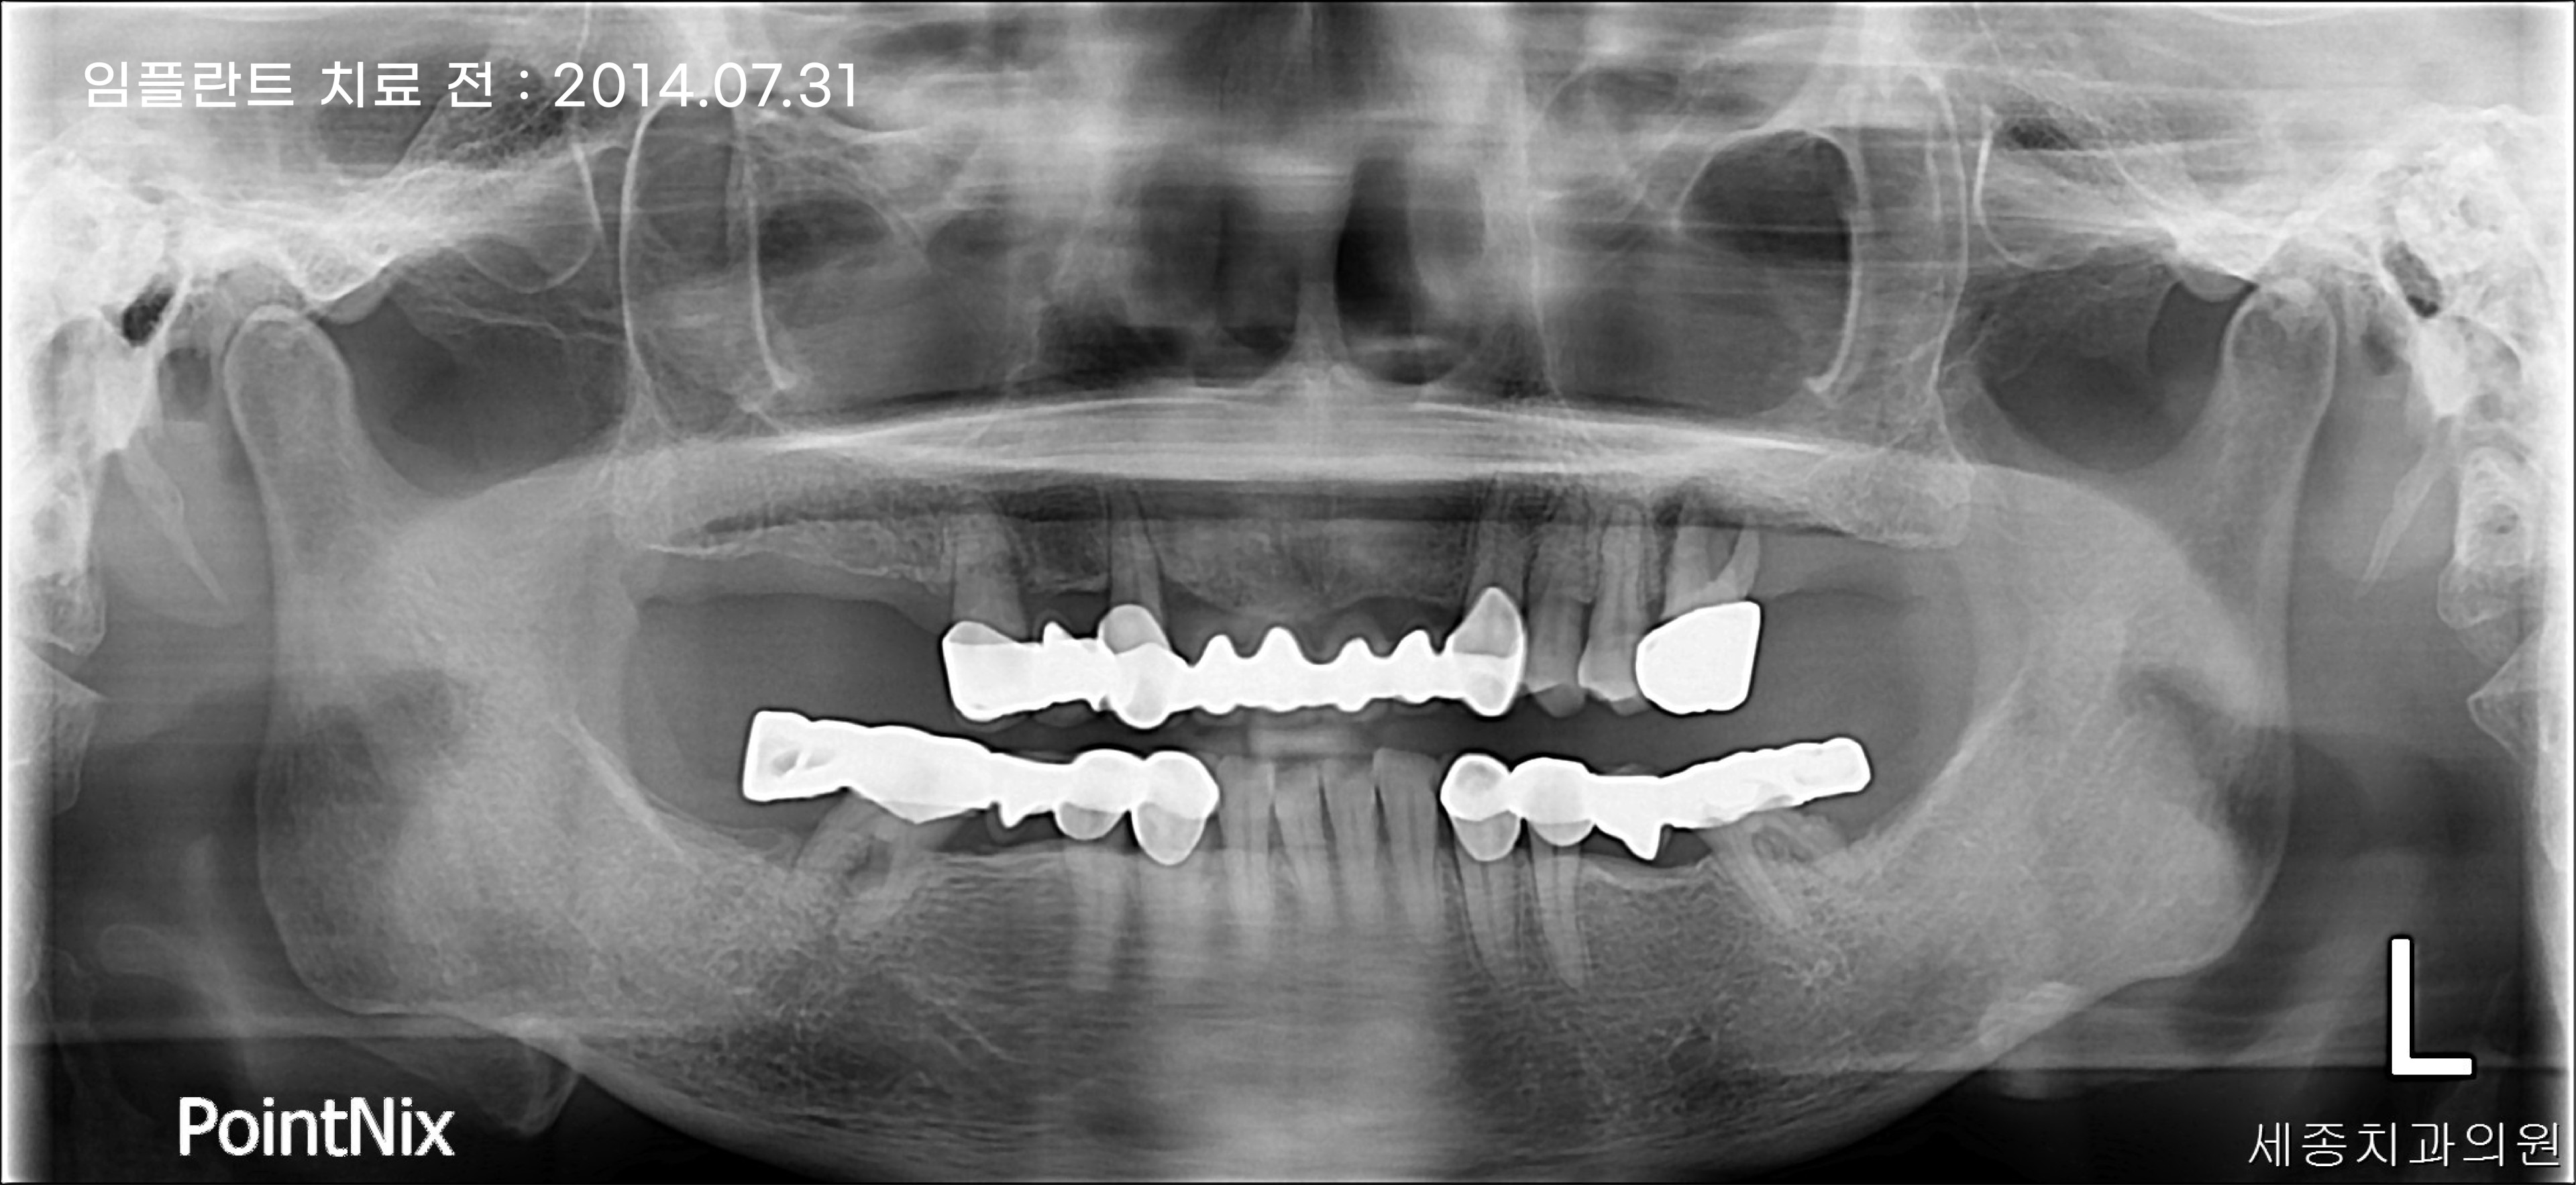

부산임플란트 세종치과 10주년 기념으로 2014년에 내원하신 환자분의 케이스를

통해 브릿지와 임플란트의 장단점을 알아보는 시간을 가져보도록 하겠습니다.

환자분의 경우 첫 내원을 했을 때 치아를 상실한 부위를 치아 브릿지로 치료를 하신 상태였는데요.

위의 파노라마 사진에서 볼 수 있듯이, 하악 기준 상실한 치아의 개수는 6개이지만 임플란트는 4개만 식립하여

1. 시술 비용 감소 2. 통증 감소 3. 회복 기간 감소 등의 장점을 얻을 수 있습니다.